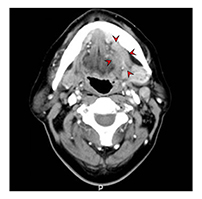

![[좌측 설암 전산화단층촬영 이미지]](../res/images/cancer/21_2_3.jpg)

[좌측 설암 전산화단층촬영 이미지]

전산화단층촬영(CT)과 더불어 임상적 병기 결정을 위한 정보를 얻는데 사용합니다. 연조직에 발생한 암종의 경우 자기공명영상이 더 선호되고 있어 설암 환자의 경우 자기공명영상이 필수적이라 할 수 있습니다. 촬영 전 구강 내 보철물은 제거하고 촬영하는 것이 상의 왜곡을 막기 위해 필요합니다.

[ 좌측 설암의 자기공명영상 촬영 이미지 ]